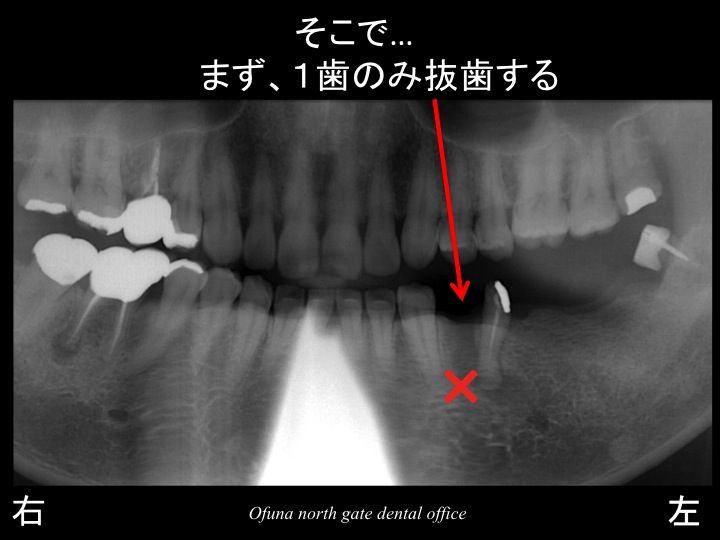

そこで以下のような治療方法を考えました。

まず、奥から3番目の歯のみを抜歯します。

そして、残った天然歯の2歯でブリッジの仮歯を作製します。